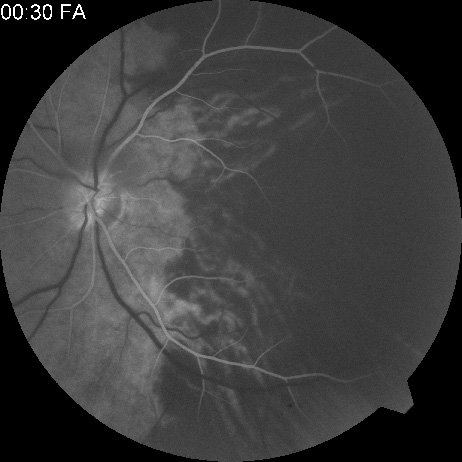

The clinical picture is typically striking. Patients present with a sudden painless loss of vision. The appearance of a cherry-red spot in the fundus is characteristic (Fig. 1).2 The cherry-red spot appears because soon after obstruction of the blood flow to the inner retina, the normally transparent retina becomes opaque and blocks the brownish-red color from the underlying choroid, which is still supplied by blood. Because the retina overlying the foveola is relatively thin, however, the normal color of the choroid is still visible in this area.3,4 Although characteristic, the cherry-red spot is not pathognomonic for central retina artery obstruction.5 Sometimes the characteristic cherry-red spot does not develop; there may be only a slight accentuation of the brownish-red color in the foveola.4 It is not known how long it takes this cherry-red spot to appear, but in a primate model, it has appeared as early as 30 minutes after obstruction.6 An afferent pupil defect is usually present.2

Fig. 1. A: Acute central retinal artery obstruction with a cherry-red spot. B and C: Intravenous fluorescein angiography. There is a delay of dye appearance in the central retinal artery, and when it does appear, it does not fill the arteries completely. D: Ocular coherence tomography (OCT) at the time of occlusion showing the increase in retinal thickness and reflectivity of the inner layers of the retina. E: Seven months later there is significant optic atrophy(G), and the OCT (F) shown now has marked thinning of the retina.

With time, the retinal opacity diminishes, generally leaving an optic nerve that is atrophic (Fig. 1). Frequently, thinned retinal arteries and veins also remain.7,8 No foveolar light reflex is evident, and a finely pigmented appearance of the macula is typical.7 In some cases, arterial collaterals develop at the optic disc.9–11 Rarely, anatomoses that exist between the central retinal artery and the ciliary arteries become visible as preretinal loops (Nettleship collaterals) after an occlusion at the edge of the disc.12,13,378In approximately 20% of patients, an embolus is evident somewhere in the arterial system.14 Emboli are discussed later.

Intravenous fluorescein angiography is useful in showing the details of the abnormal circulation of a central retinal artery obstruction (Fig. 1). The principal abnormality is the delay in the appearance of the dye in the central retinal artery and its branches.2 Rather than the central retinal artery and its branches filling rapidly, considerable time may elapse before the entire arterial system is filled.15 The filling of the retinal arteries is often abnormal, with the fluorescein partially filling an artery (a dye front) or hugging the vessel wall, as in normal venous filling.15

Optic coherence tomography (OCT) of an acute central retinal artery occlusion shows a slight increase in the thickening of the retina and reflectivity of the inner layers of the retina that correspond to the opacity seen clinically (Fig. 1).409 With time, the disc becomes atrophic and the retina thinner.